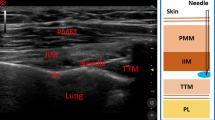

Ultrasound-guided TPVB

Ultrasound-guided TPVB was performed by one experienced anesthetist with a low frequency (2 ~ 5 MHz) curved array transducer (SonoSite M-Turbo; SonoSite Inc., Bothell, WA, USA). Patients were placed in the lateral position with the side to be operated upwards. Using aseptic precautions, the T4 and T5 paravertebral space was located by counting from the 12th rib to the 4th rib. TPVB was performed at the T4 paravertebral space first. The transducer was placed at an oblique transverse position along the long axis of the rib and tilted until the transverse process, the internal intercostal membrane and the pleura were visualized. After infiltration with 2 ml of 1% lidocaine, a 22-gauge, 120-mm stimuplex needle (Stimuplex® D; B. Braun; Melsungen; Germany) was advanced from lateral to medial with in-plane technique under real-time ultrasound guidance. Once the needle passed through the internal intercostal membrane, 10 ml of 0.4% ropivacaine was injected. Using the same technique, another 10 ml of 0.4% ropivacaine was injected at the T5 paravertebral space.